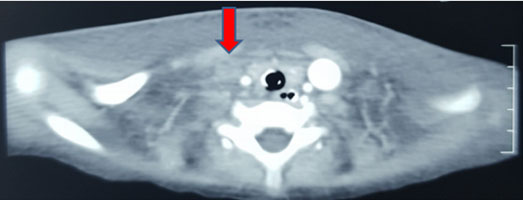

Initial investigation profile showed hemoglobin (Hb) of 8.5 g/dL with microcytosis and hypochromia. Some atypical lymphocytes and increased platelets were noted. Blood culture grew Staphylococcus aureus sensitive to penicillin. Erythrocyte sedimentation rate (ESR) using the Westergrens method was normal (20 mm/h). Reticulocytes were 7.9%. Hepatitis and venereal disease research laboratory (VDRL) serology were negative. Pleural aspirate had red cells with 1600 white blood cells/mm3 which reduced to 320 white blood cells/mm3 on a repeat tap five days later. Biochemistry analysis [glucose 6.7 mmol, total protein 1 g/L, albumin 18, lactate dehydrogenase (LDH) 234 U/L] showed effusion was transudative in nature. No malignant cells seen. Culture was negative and no acid-fast bacilli (AFB) were seen. Ascitic fluid also had red blood cells and 160 white cells/ mm3, cultures were negative, glucose 6.7 mmol, total protein 19 g/L, Alb 10.2 g/L, LDH 234 U/L. The serum ascites albumin gradient was >1.1 g/dL indicating portal hypertension, negative for malignant cells. Her liver functions deteriorated over the course of admission. Antinuclear antibodies (ANA) and double stranded DNA (DsDNA) done to rule out SLE were also negative. Computed tomography (CT) scan revealed multifocal segments of venous thrombosis involving right internal jugular vein (Figure 3), left brachiocephalic, main portal vein, superior mesenteric, and hepatic veins. There was no obvious neck thoracic or abdominopelvic mass. Moderate ascites were with bilateral pleural effusion. Liver showed inhomogeneous enhancements/nutmeg liver with thrombosis of hepatic veins (Figure 4). Liver biopsy was contemplated, however poor general condition and deranged coagulation profile precluded the invasive procedure.

Figure 3: Thrombosis of right internal jugular vein.